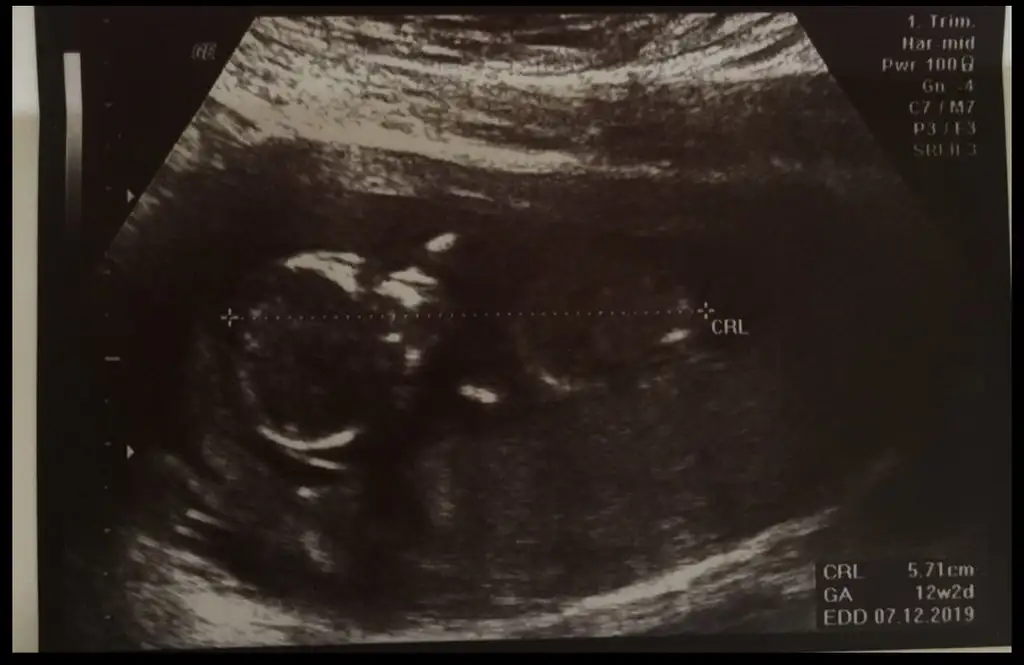

Nub yöntemine göre cinsiyet tahmini

Gittim canim dr kiz gibi dedi ama kesin soyleyebilmem icin 16.haftayi bekleyecegiz dedi ama nubu bana gore karsiya bakiyor onda da kesin konusmadi erkek olsa yanilma olmaz bu haftalarda ama bazen kizda yanilma olabilir bekleyelim dedi